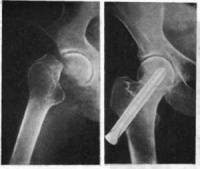

Изученный материал показывает отсутствие на настоящем этапе оперативных технологий сочетающих оба направления. Перспективным вариантом улучшения условий консолидации оскольчатых переломов бедра представляется комбинированный остеосинтез. У 26 пострадавших в различных комбинациях нами использовано 6 вариантов скрепителей. Основной целью в этих случаях было достижение наиболее прочной фиксации перелома при максимально точной репозиции отломков и обеспечение возможности нагрузки конечности в ранние сроки. Такое улучшение условий консолидации сказалось на сроках появления клинико-рентгенологических признаков сращения (4-5недель после операции), более выраженной плотности и организованной архитектонике костной мозоли, отсутствии признаков еѐ гиперпластического или иного патологического развития.

Наиболее хорошо это видно на цифровых рентгеновских снимках. Средние сроки сращения оскольчатых переломов бедра при комбинированной фиксации составили 7,5-8 месяцев при удовлетворительных функциональных исходах, что позволило пострадавшим приступить к работе. Таким образом, можно заключить, что при оскольчатых переломах бедренной кости комбинированный остеосинтез позволяет оптимизировать условия консолидации отломков.